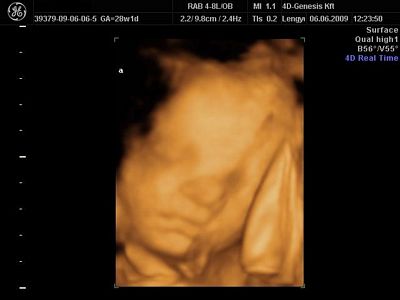

Mi voltunk tegnap 4d-n,ugyanott,mint 16 hetesen,de most sajnos a másik nő volt,hááát,elég nagy a különbség a munkájuk között.Csinált az egy órás uhu alatt 8 képet,az is mind ugyanolyan.Majd felteszem.

Rendben vannak,977 gramm Nonó,és 1170 Balász.5 nap különbség van köztük,Balázs csontra annyi idősnek mérte a gép,mint amennyi,28+1 voltunk tegnap,Nonó 5 nappal kissebb.Viszont érik a lepényem(grannum I-II),sokkal több pihit és kevesebb streszt írtak elő,de azt mondták aggódni ne aggódjak ezen.

És a képek:

Nonó az elsőn,Bazsi a másodikon: